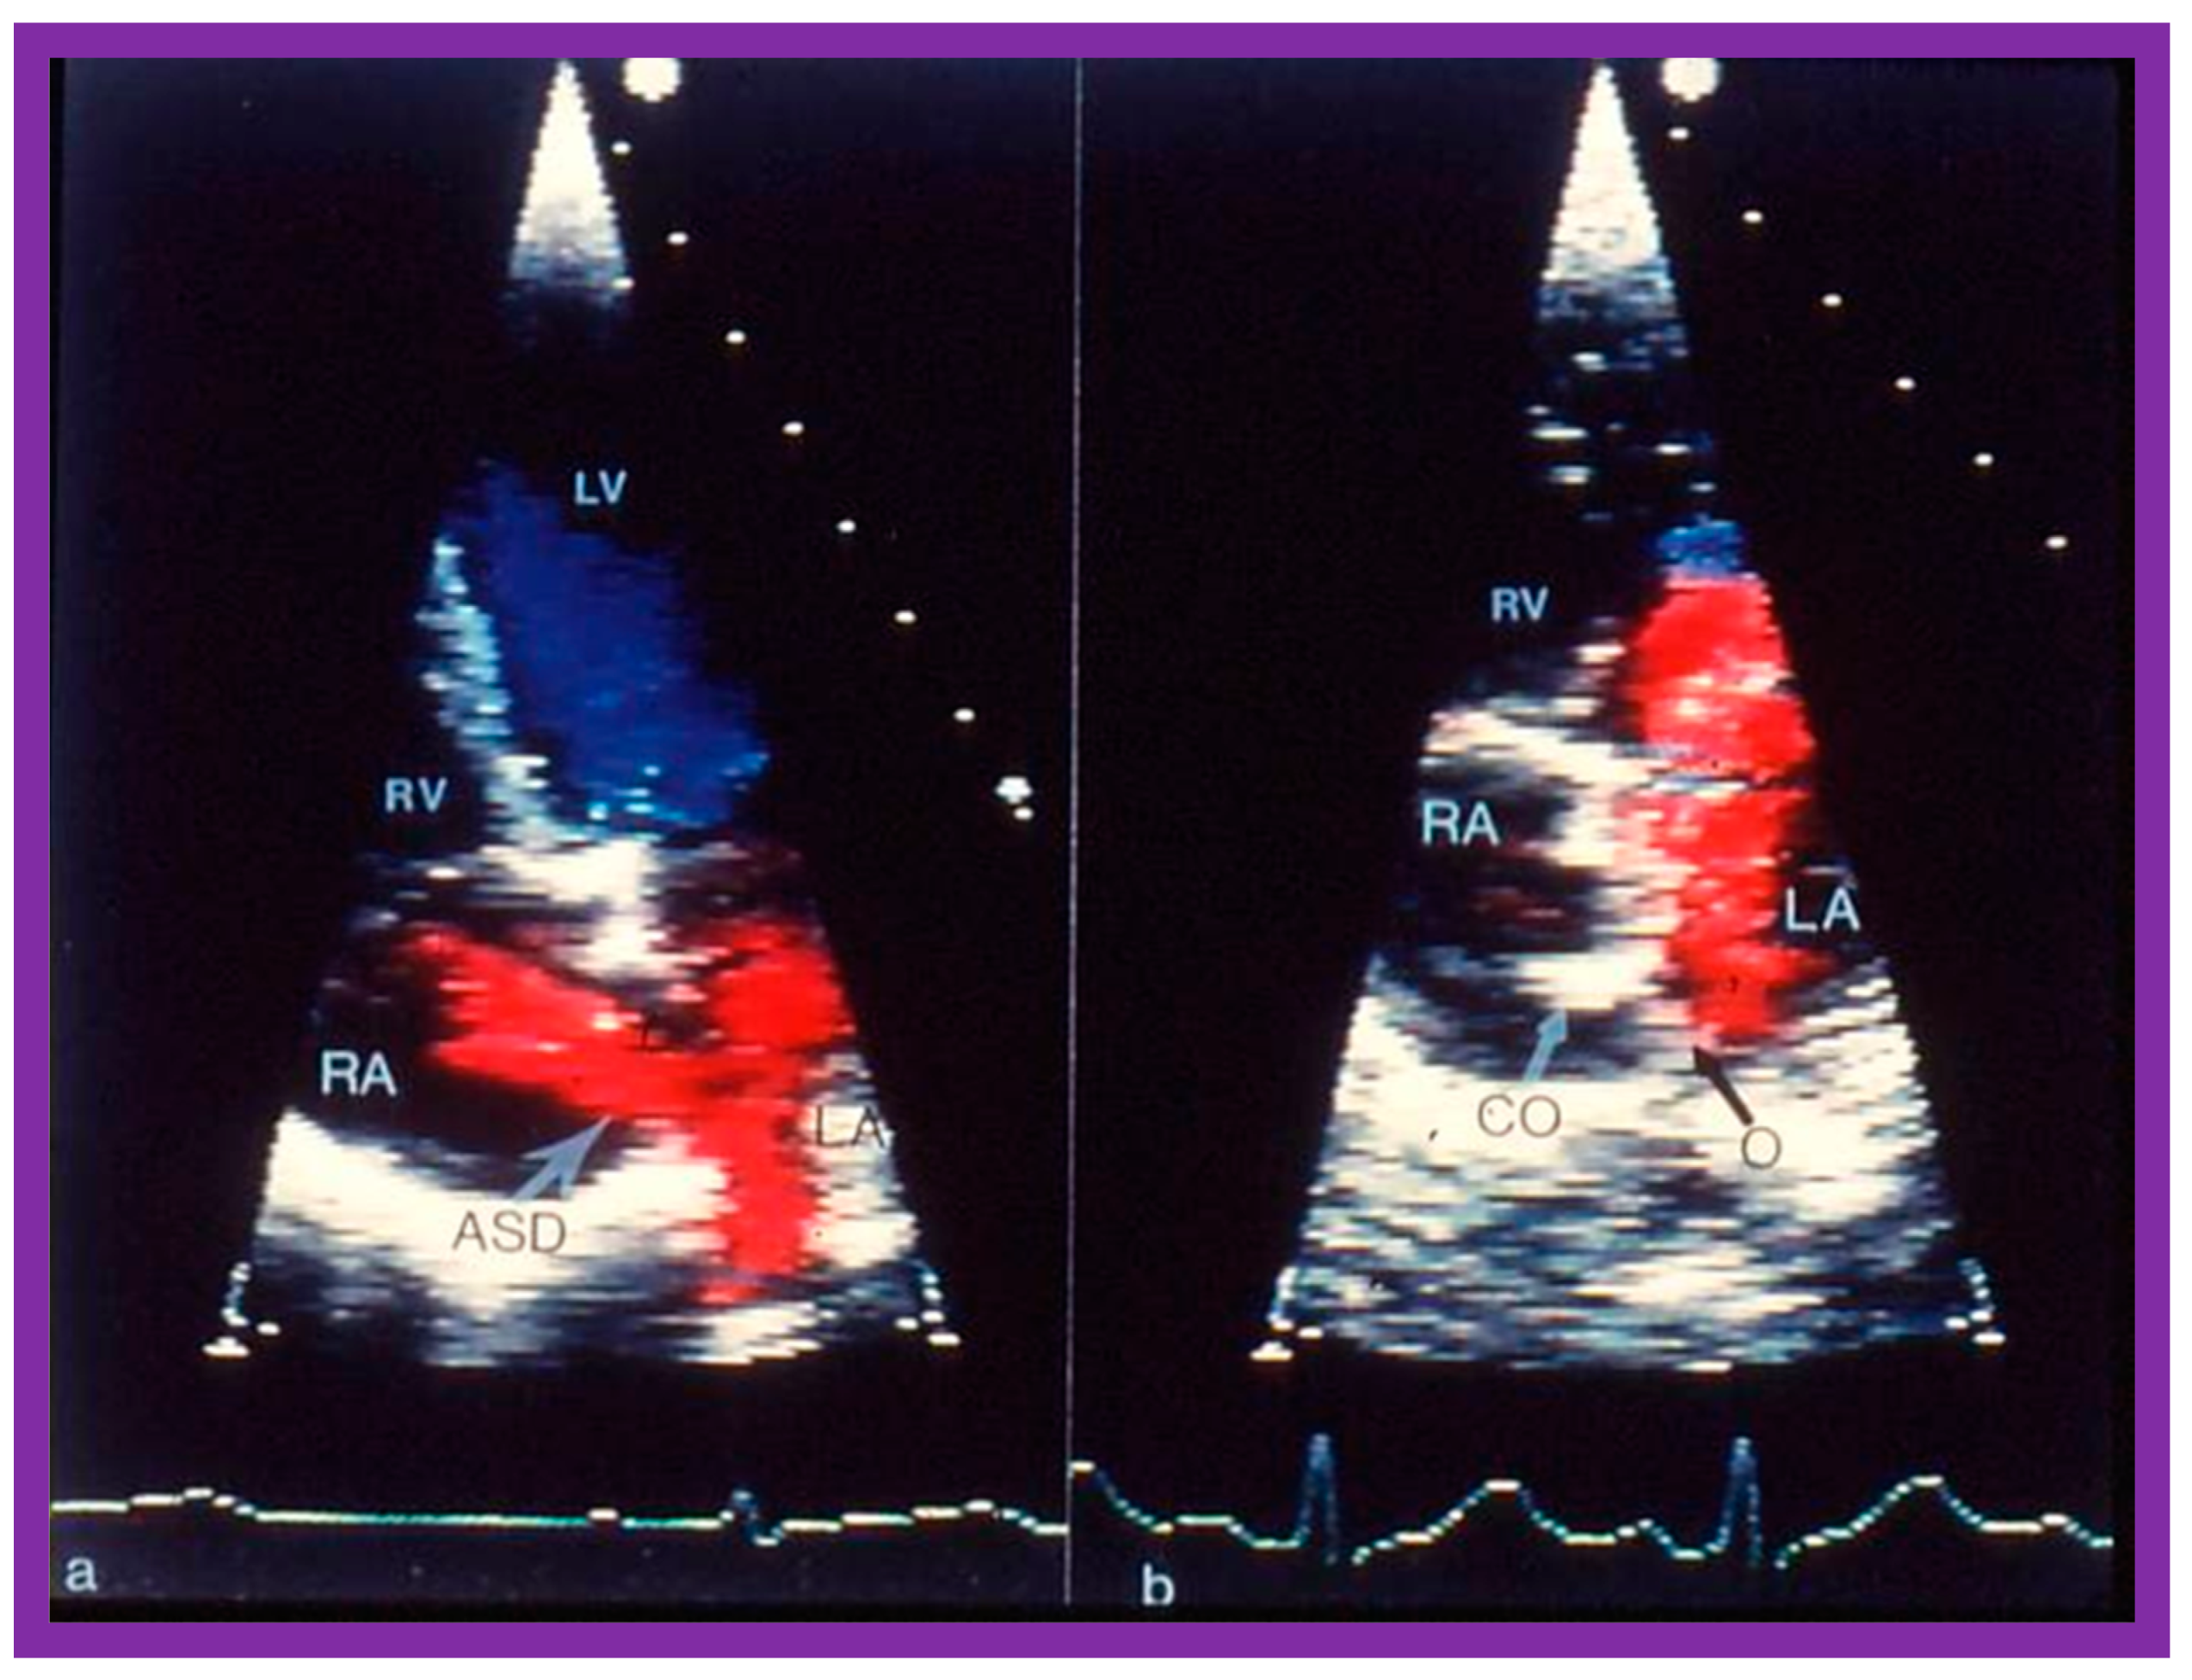

2. Diagnosis

7. Balloon Sizing

8.6. Multiple Defects

9. Follow-Up after Device Occlusion